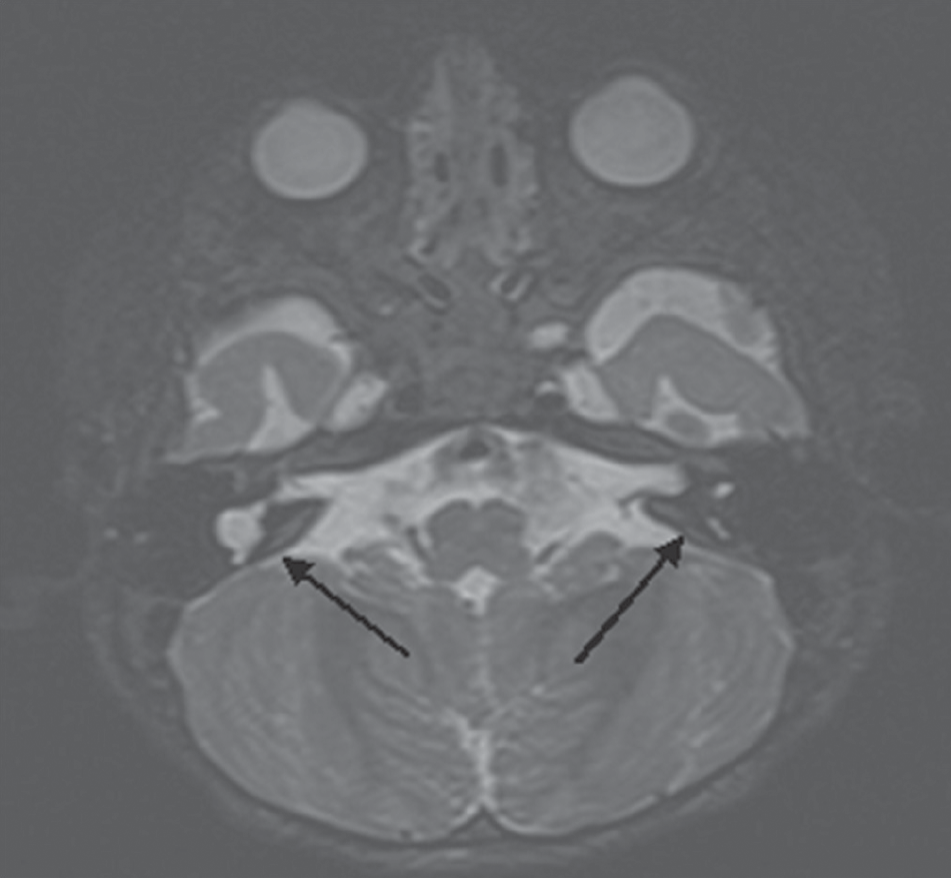

According to various authors, 20% of children with sensorineural hearing loss or deafness, anomalies in the structure of the temporal bones are determined according to the results of computed tomography. Cochlear implantation in the presence of cochleovestibular malformations is associated with a number of difficulties. These include the peculiarities of cochleostomy and placing of the electrode inside the cochlea, the risk of damage to the facial nerve due to its abnormal location, intraoperative liquorrhea, which can lead to the development of bacterial meningitis in the postoperative period, as well as the risk of penetration of the electrode into the internal auditory canal. In this research, we present our method of performing cochlear implantation in case of a malformation in the development of the inner ear (common cavity). The method expands the possibilities of cochlear implantation for e auditory perception in patients with this pathology.